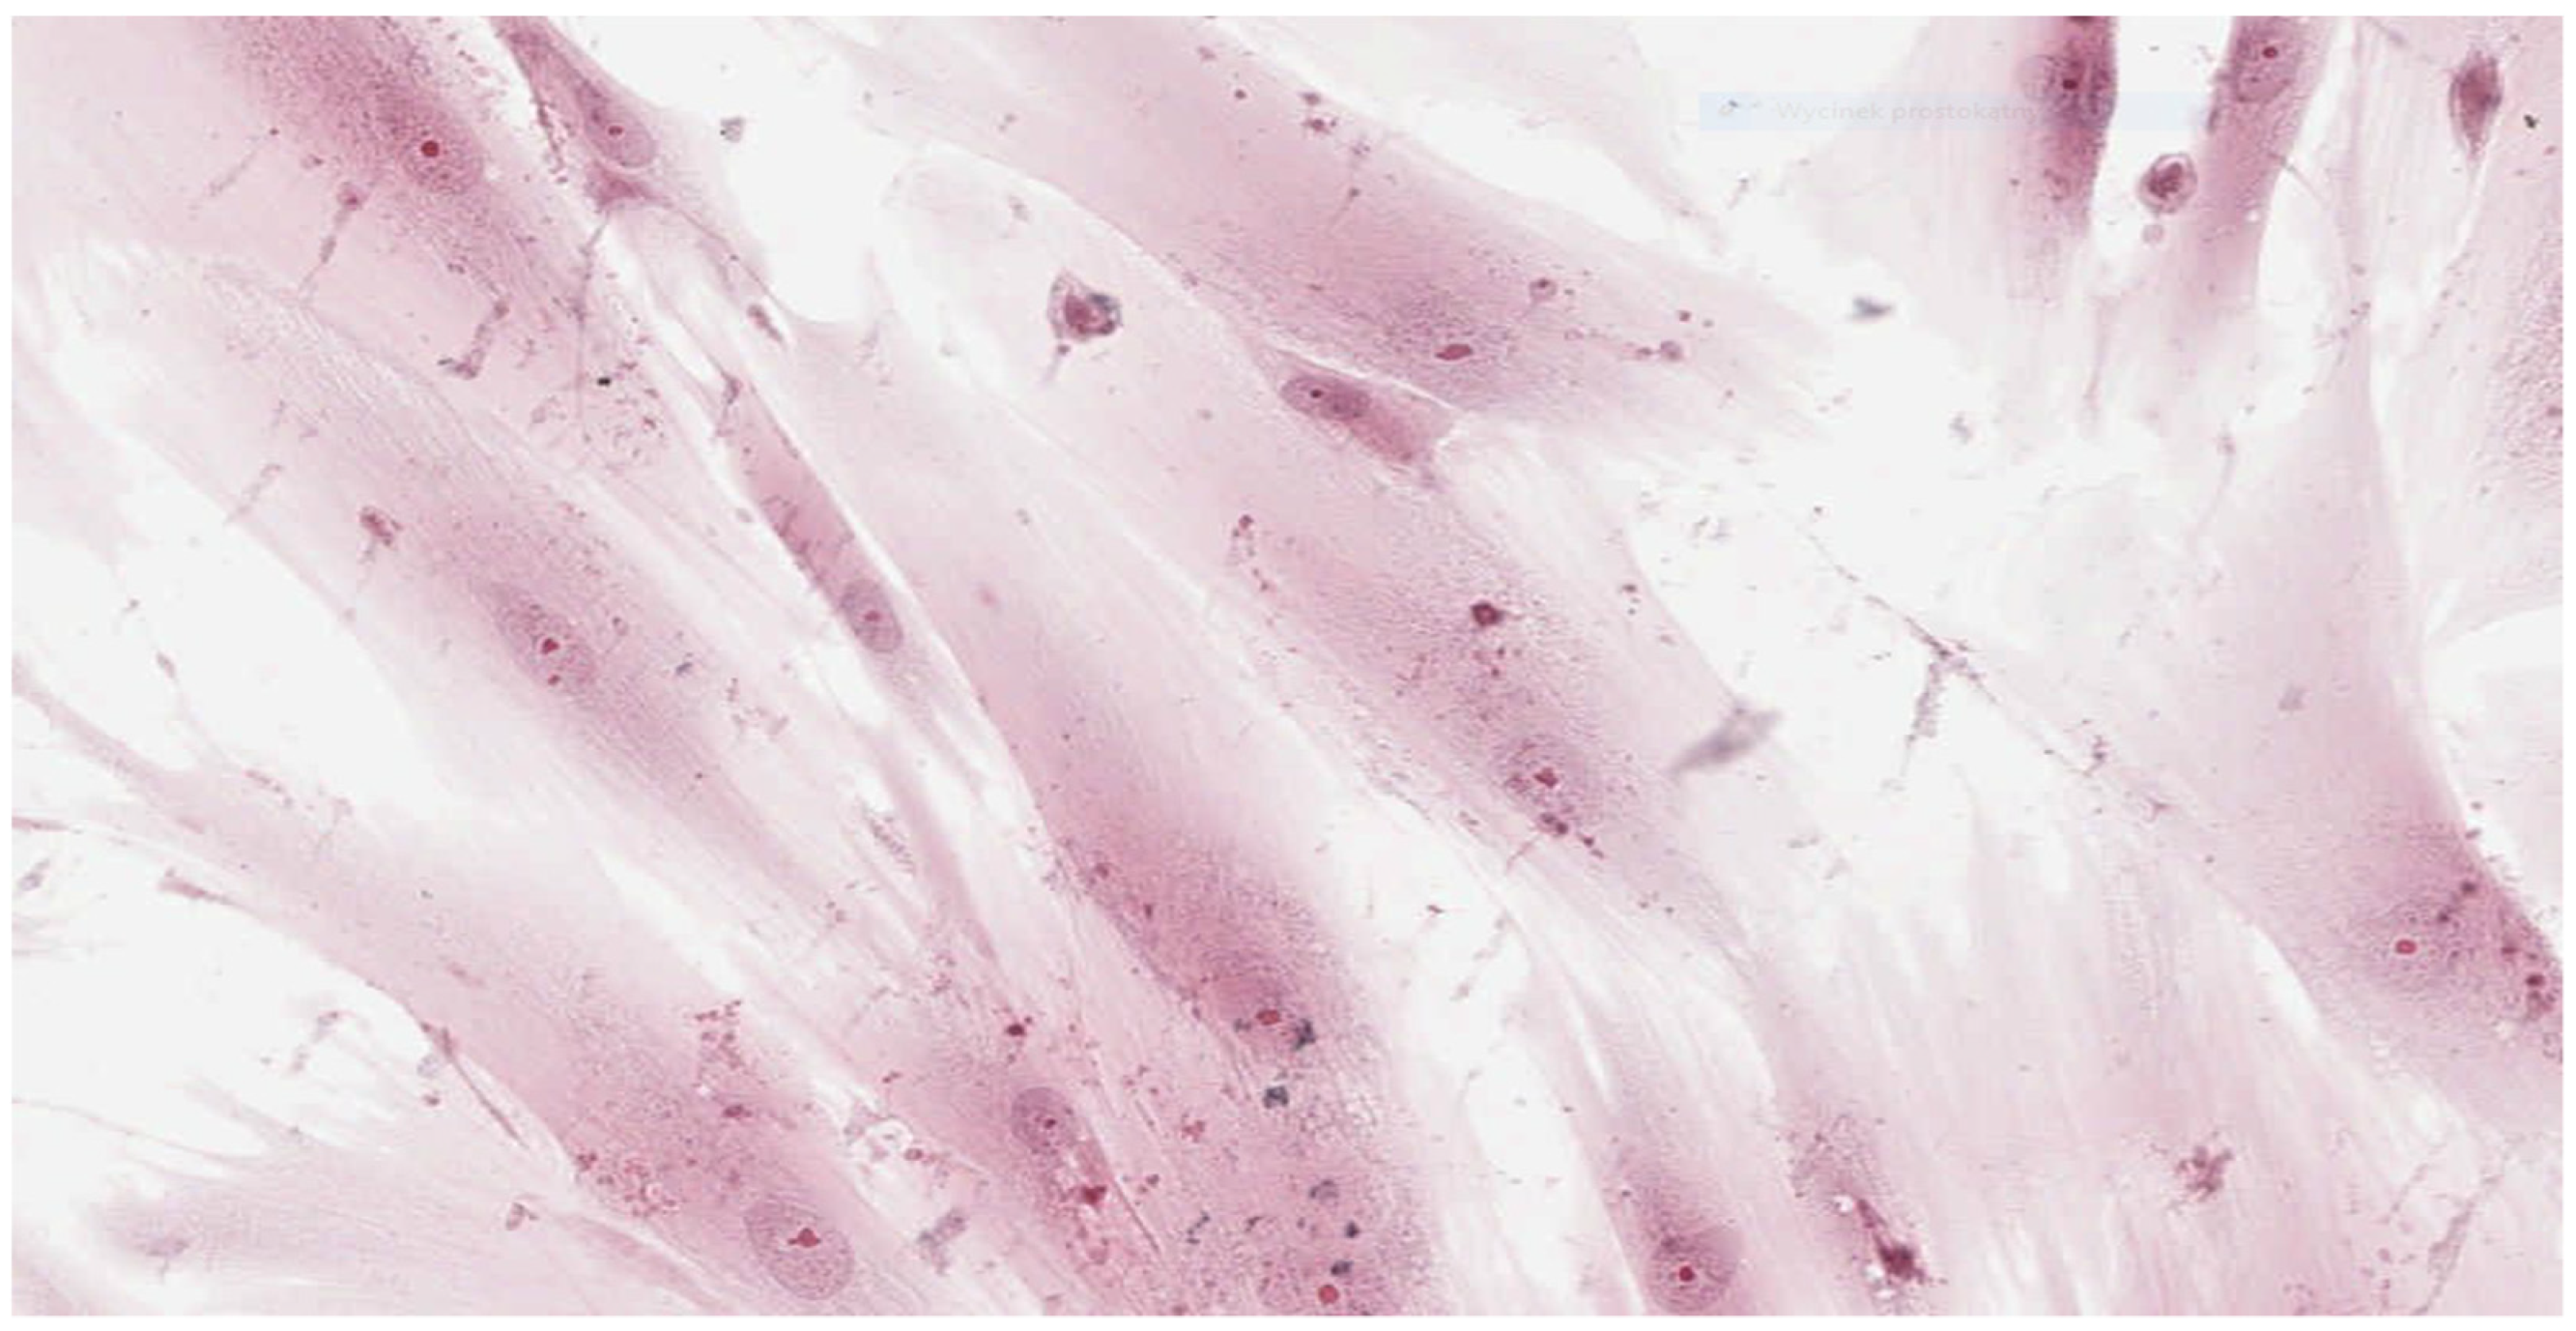

Figure 1 and Figure 2 show the histopathologic images of control cells culture (K) at 100× and 200× magnifications. It is a homogeneous population of proliferating spindle-shaped fibroblasts with tapering ends of the cells; there is no cell lysis and no reduction of cell growth. Oval nuclei can be in the central part of the cell with distinct ruby nucleoli. Intense cytoplasmic staining indicates active protein synthesis. Numerous visible shape changes occurred during mitosis. This image represents grade 0 (no reactivity) in qualitative morphological grading of cytotoxicity according to INTERNATIONAL STANDARD ISO 10993-5:2009(E).

Figure 1. Image of control culture (K); 100× magnification.